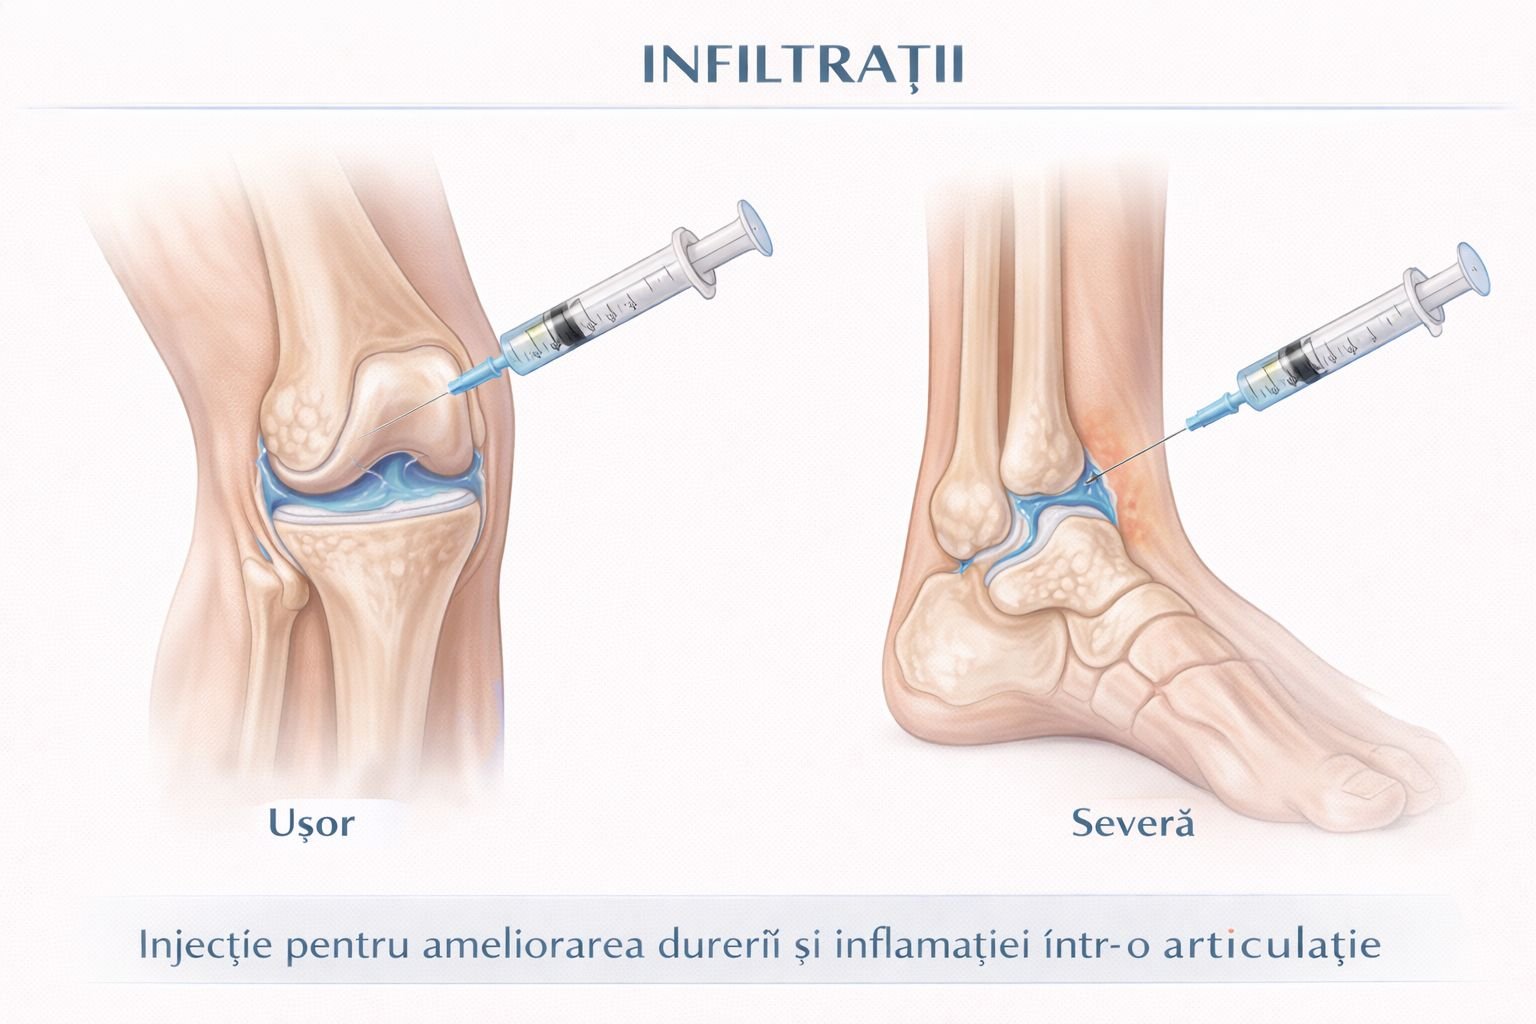

- Infiltrațiile cu corticosteroid: soluția rapidă pentru durere și inflamație articulară